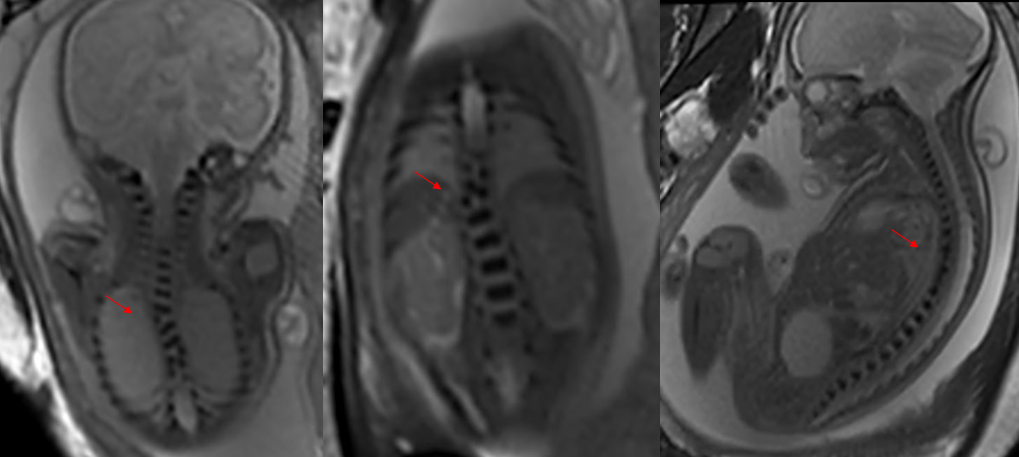

每33秒出生一个缺陷儿

根据2012年卫生部《中国出生缺陷防治报告(2012)》白皮书指出,我国是出生缺陷高发国家之一,新生儿出生缺陷发生率约为5.6%,每年新增出生缺陷患儿约90万例,目前已知的人类出生缺陷疾病达8000—10000种。预防出生缺陷是全球重大医学课题,亦是民生健康刚需。

出生缺陷,会给家庭带来沉重的精神和经济负担,严重影响家庭的幸福和生活质量。